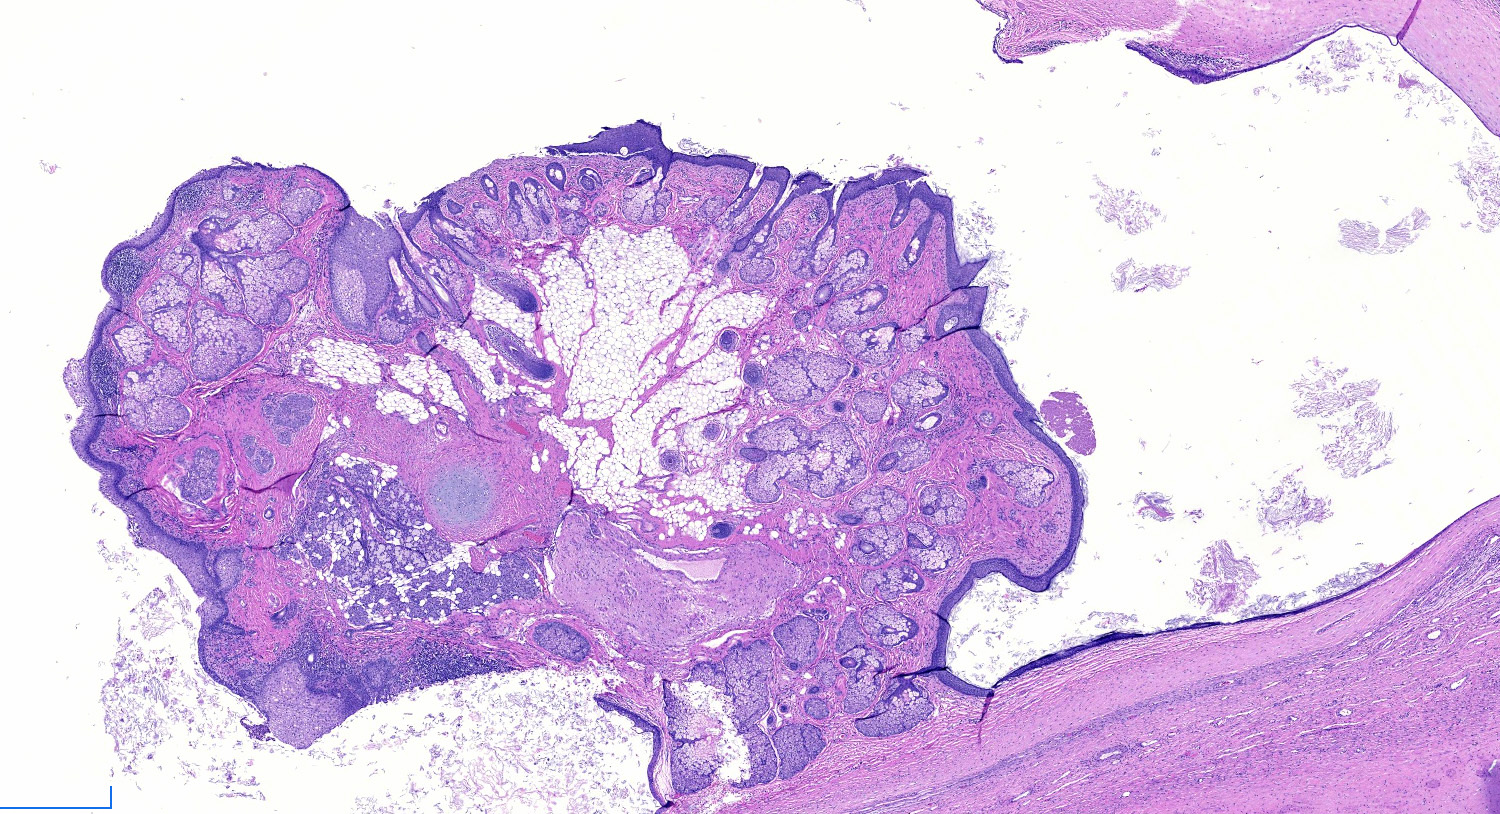

Gross description

- Smooth cyst that may contain hair, teeth, cartilage, bone or sebaceous material

- Generally < 10 cm

- Raised protuberance in cyst wall (Rokitansky nodule)

- Reference: StatPearls: Cystic Teratoma [Accessed 29 July 2021]

Gross images

Microscopic (histologic) images